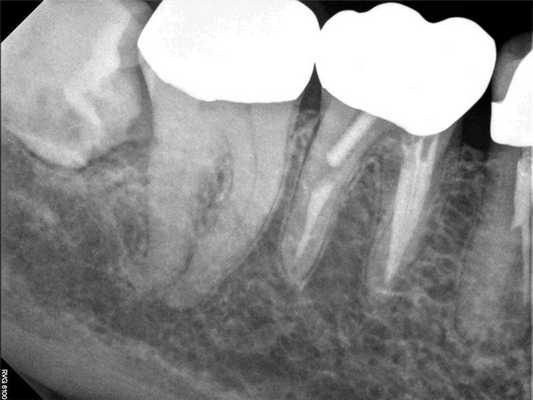

75-летний пациент мужского пола обратился за стоматологической помощью с основной жалобой на сильную, плохо локализованную боль с правой стороны челюсти и лица, которая началась еще неделю назад. Он описал боль как пульсирующую и указал, что она распространяется от средней линии лица до правого уха как в проекции верхней, так и нижней челюсти. Пациент также сообщил, что воздействие тепла усугубило симптомы, и он может облегчить боль только держа во рту холодную воду. Небольшое облегчение было отмечено при пероральном приеме комбинации 600 мг ибупрофена плюс 500 мг ацетаминофена. Хотя такая основная жалоба пациента, как правило, связана с патологией дегенеративного пульпита, но в ходе клинического осмотра и рентгенологической диагностики не было обнаружено никаких примечательных изменений. Зубы с правой стороны верхней и нижней челюсти не демонстрировали признаков чрезмерной чувствительности на тепловые раздражители, перкуссию и пальпацию. Также у пациента не было идентифицировано признаков припухлости или формирования свищевого хода, подвижность зубов была в границах физиологического диапазона, а глубина пародонтального зондирования не превышала физиологической границы. На первичных рентгенограммах зубов 30 и 31 была верифицирована нормальная ширина пространства пародонтальной связки и ретенция 32 зуба. В структуре 32 зуба визуализировалась небольшая область просветления, находящаяся близко к дистальной поверхности корня 31 зуба (фото 2-3).

Фото 3. Клинический случай 1. Рентгенограмма области дистального правого квадранта нижней челюсти без выраженных признаков изменений. Наличие ретинированного моляра.

Чтобы купировать выраженные болевые ощущения пациента была проведена блокада нижнего альвеолярного нерва посредством 3,4 мл 0,5% раствора бупивакаина с концентрацией эпинефрина 1:200000. Через 5 минут после анестезии пациент сообщил о полном разрешении боли. Учитывая факт купирования болевых симптомов после выполнения анестезии, было предположено, что этиология таковых является одонтогенной. В ходе выполнения повторной рентгенографии была визуализирован участок внутрикоронковой резорбции непрорезавшегося 32 зуба. Пациент был направлен к челюстно-лицевому хирургу с целью удаления проблемного зуба. После экстракции больной сообщил, что все симптомы боли разрешились. После выполнения экстракции был подтверждён диагноз внутрикоронковой резорбции 32 зуба.

Фото 4. Клинический случай 1. После выполнения анестезиологической блокады было проведенного повторное рентгенологическое обследование, которое позволило обнаружить внутрикорональную резорбцию в структуре ретинированного моляра, которая спровоцировала развитие симптомов необратимого пульпита.